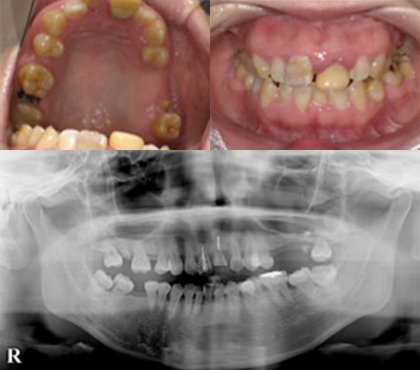

症例

奥歯は欠損放置による骨量不足のため骨増生を行い、前歯は破折歯をジルコニアセラミックとインプラントで補綴しました。前歯4本はオールセラミックにて修復しています。

修復前

修復後

| 治療費用 |

インプラント 1本 385,000円×4本 オールセラミック 1本 130,000 円×1本 骨増生 55,000円 |

|---|---|

| 治療のリスクについて | 骨増生の際には、一時的に腫れを伴うことがあります。当院では、麻酔専門医による静脈内鎮静法を併用し、腫れを抑える薬剤を適切に投与することで、患者様のご負担を軽減できるよう努めております。 |